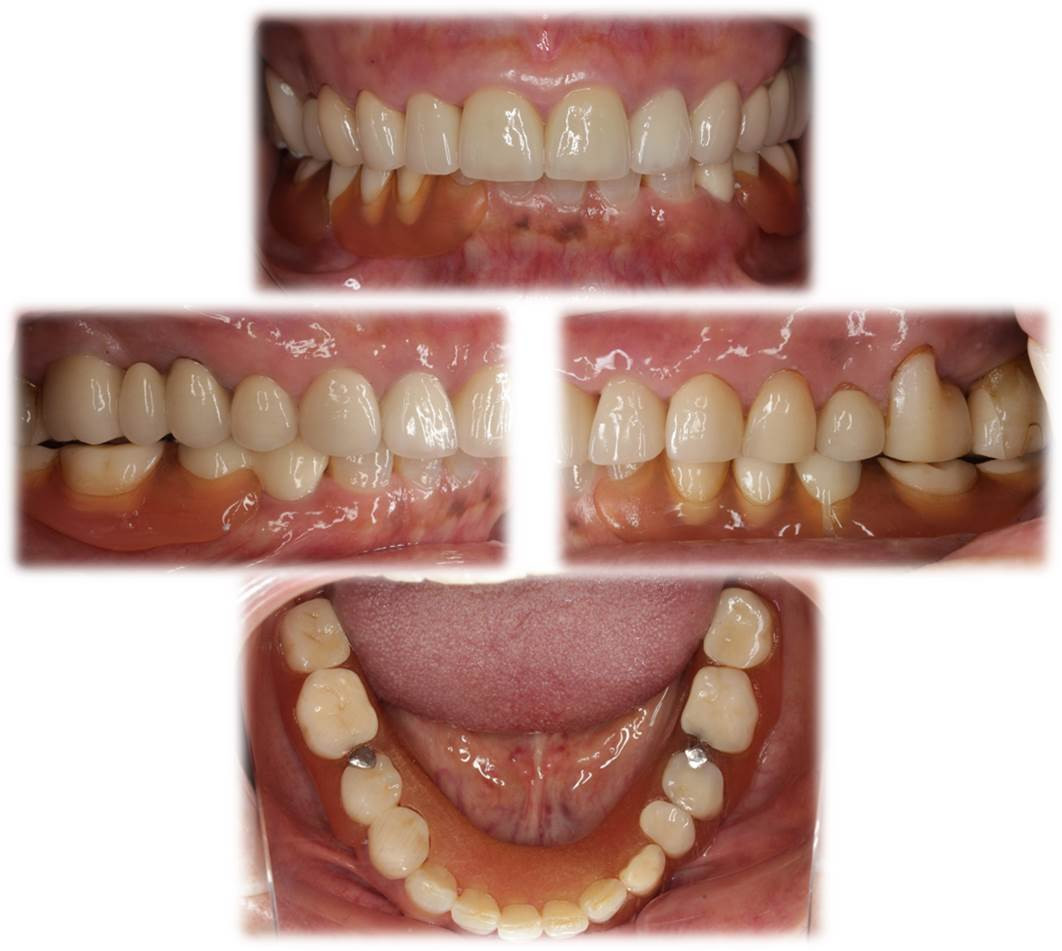

画像の患者様も下顎にナイロンデンチャーを使用しており、入れ歯の人工の歯の部分には対合歯とは咬み合わせていないにも関わらず、義歯性潰瘍を生じ続けておりました。